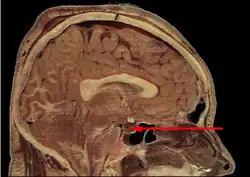

L'hypophyse se trouve dans une cavité osseuse, la fosse hypophysaire qui se situe dans l'os sphénoïde. Elle est protégée par la selle turcique. Elle est reliée à une autre partie du cerveau appelée l'hypothalamus par une tige hypophysaire (également appelée tige pituitaire). Elle produit des hormones qui gèrent une large gamme de fonctions corporelles, dont les hormones trophiques qui stimulent les autres glandes endocrines. Cette fonction lui a valu de se faire appeler par les scientifiques « glande maîtresse » du corps, mais aujourd'hui on sait que l'hypophyse est régulée par les hormones (neuro-hormones) émises par l'hypothalamus.

Anatomie

L'hypophyse est divisée en deux lobes : l'antéhypophyse (adénohypophyse) en avant, et la posthypophyse (neurohypophyse) en arrière. L'adénohypophyse dérive du plafond de la cavité buccale primitive (stomodeum), tandis que la neurohypophyse est une extension de l'hypothalamus, relié à celui-ci par la tige pituitaire, et contient les axones de neurones dont les corps cellulaires se trouvent dans l'hypothalamus. On peut également trouver entre l'antéhypophyse et la posthypophyse, une troisième structure, l'hypophyse intermédiaire, bien développée chez certaines espèces animales[Lesquelles ?] : chez l'humain, l'hypophyse intermédiaire (pars intermedia) est seulement visible en période fœtale et jusqu'à l'âge de dix ou vingt ans ; chez l'adulte, il subsiste quelques structures kystiques (follicules, restes de la poche de Rathke), ainsi qu'un infiltrat chromatophile basophile.

Exploration

Imagerie